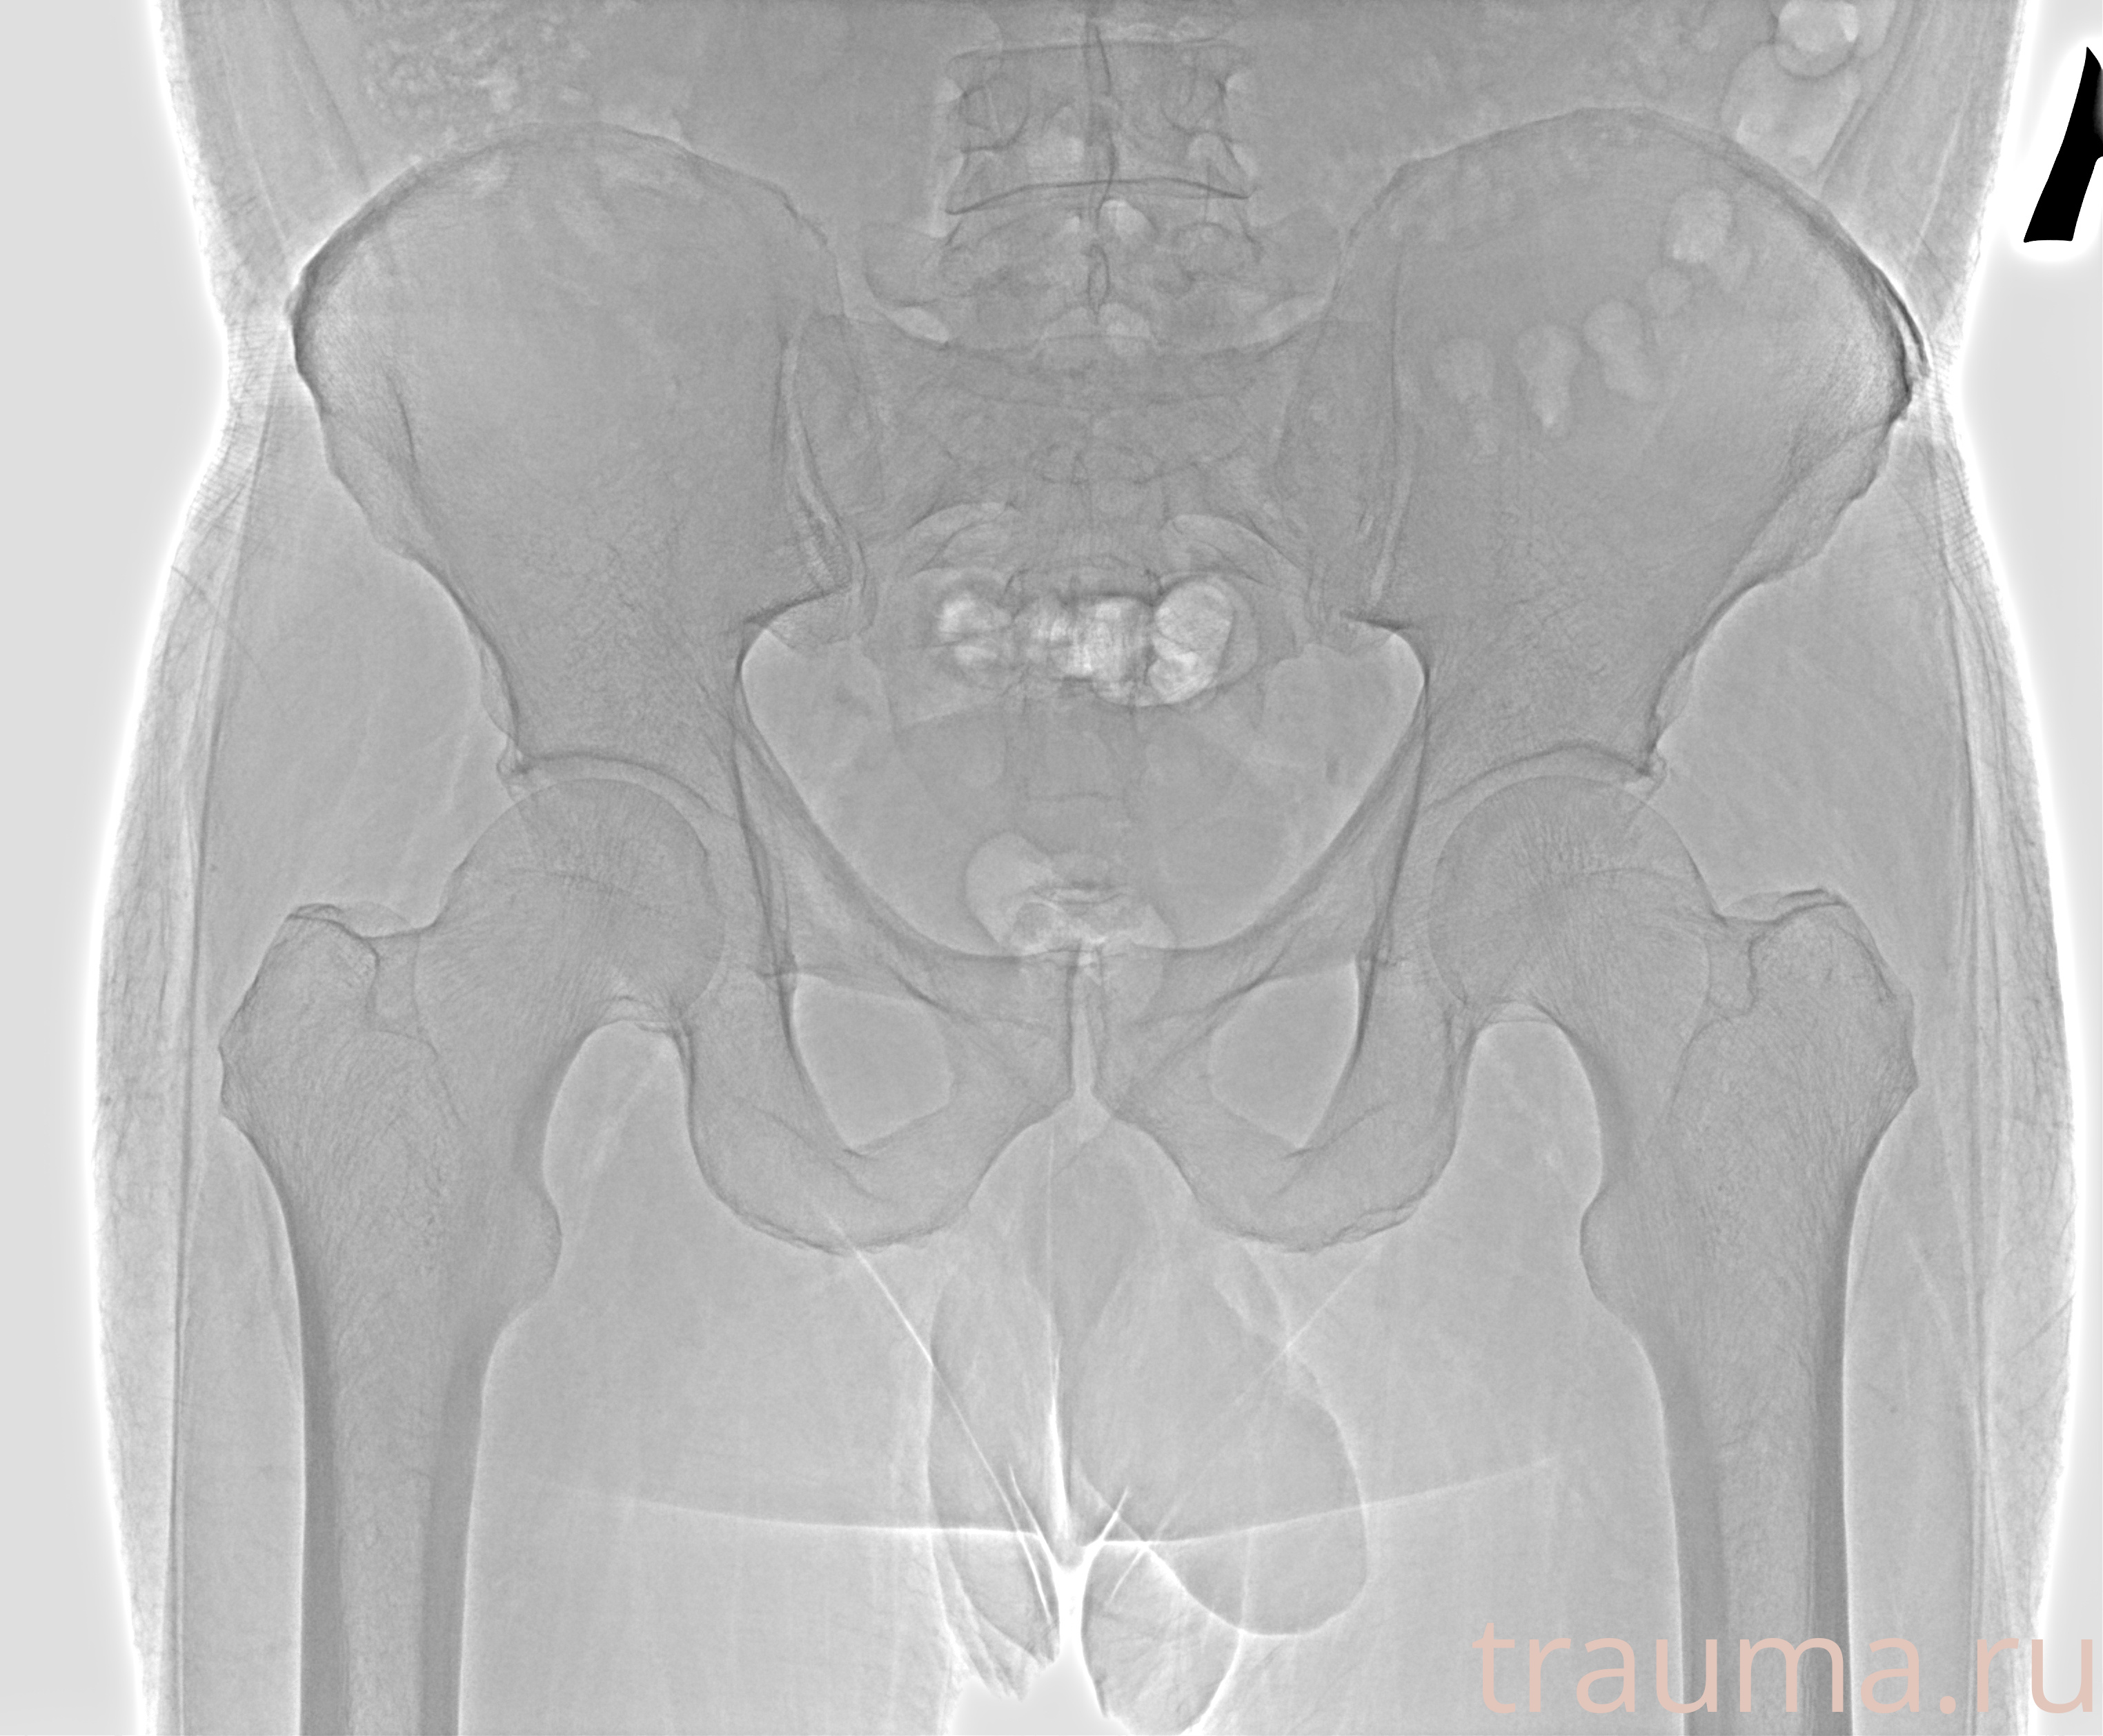

Рентгенограммы

Рентген на дому: по вашему адресу приезжает врач-рентгенолог, травматолог-ортопед с мобильным рентгеновским аппаратом, проводит диагностику травмы или заболевания, делает необходимые рентгенограммы, дает рекомендации по дальнейшему лечению. Получить качественные снимки в домашних условиях возможно благодаря уникальной методике, разработанной МосРентген Центром для института  Склифосовского